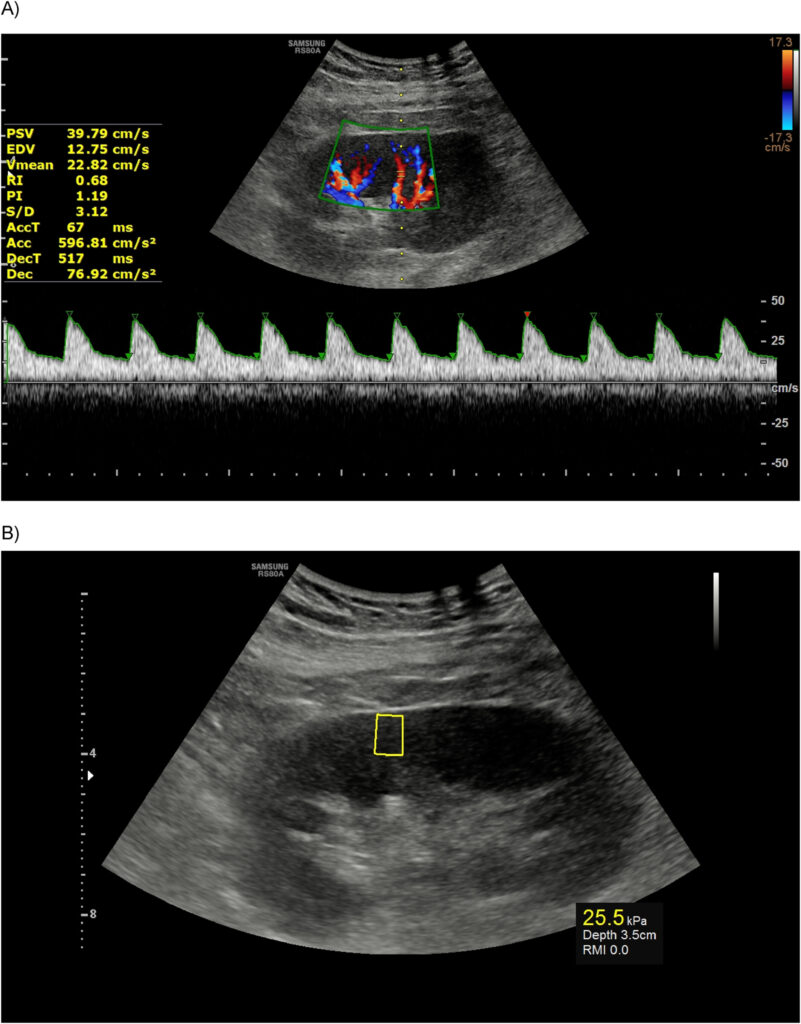

A prospective cross-sectional study of 60 consecutive adult kidney transplant recipients was done. Patients with creatinine > 1.5 mg/dL and a minimum interval of 3 months from renal transplant surgery were recruited. All patients underwent both Doppler US and US elastography. A direct head-to-head comparison was made. A glomerular filtration rate (eGFR) < 50 was regarded as delayed graft rejection. A resistive index (RI) value ≥ 0.79 was considered abnormal.

RI was more strongly correlated to age, diabetes mellitus, and hypertension with Pearson correlation coefficients of 0.414, 0.390, and 0.386, respectively, while stiffness (kPa) exhibited a stronger correlation to the time period since surgery. Using radiological findings to estimate observed eGFR showed an adjusted R2 of 0.135. Doppler US alone, US elastography alone, and combined Doppler US + US elastography + clinical data, respectively, showed area under curve (AUC) values of 0.668 (95% CI = 0.535 to 0.735), 0.641 (95% CI = 0.507 to 0.761), and 0.792 (95% CI = 0.667 to 0.886) in detecting delayed graft rejection. Estimating RI using clinical and US elastography findings showed AUC of 0.811 (95% CI = 0.689 to 0.901), with sensitivity of 61.5% (95% CI = 40.6 to 79.8) and specificity of 91% (95% CI = 76.3 to 98.1).